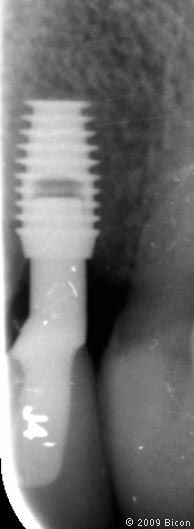

24. Рентгеновский снимок после операции.

64. Рентгенограмма после установки

65. Рентгенограмма после установки